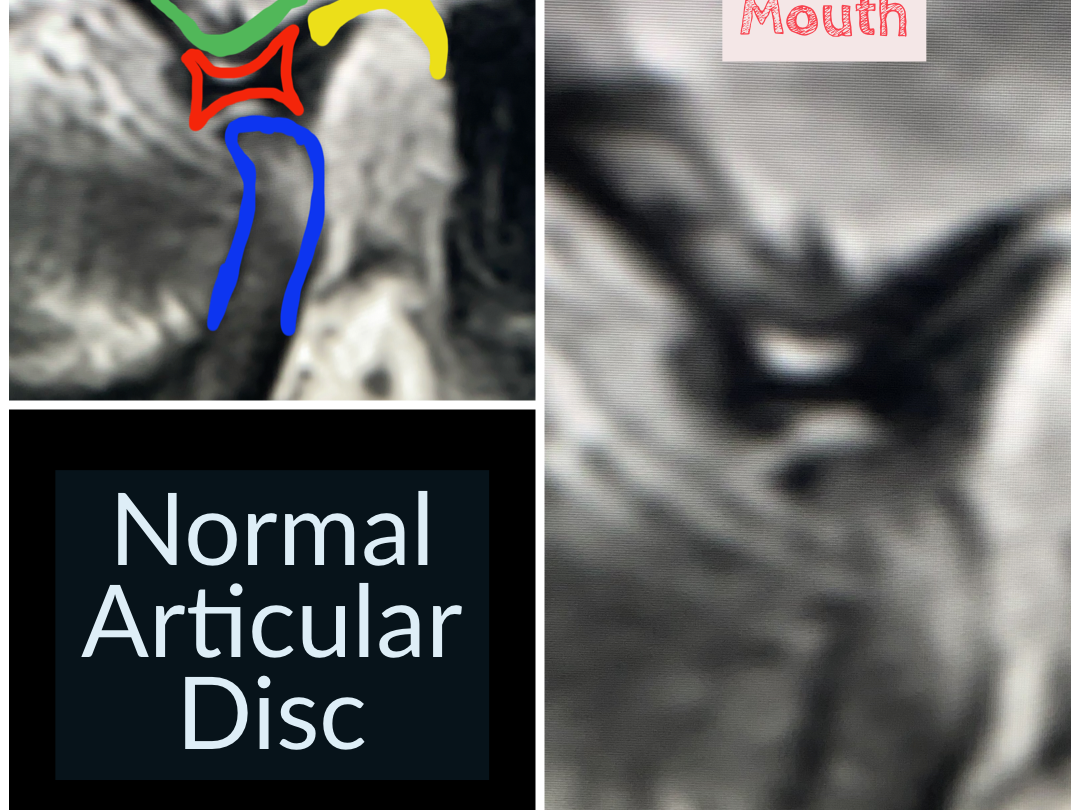

TMJ Disc Dislocation